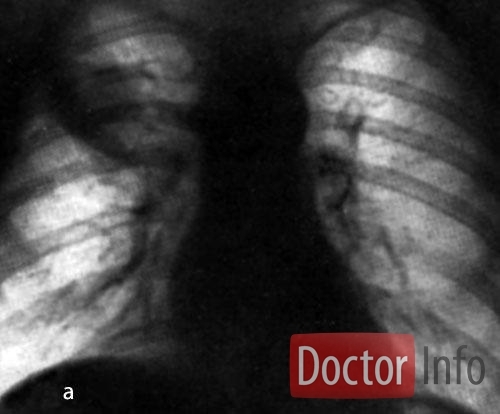

Основными возбудителями являются пневмококки различных типов, другие наиболее частые бактерии: стафилококки, клебсиелла пневмонии, гемофильная палочка (Афанасьева-Пфейфера), стрептококки. Чаще всего возникновению пневмонии предшествует другая инфекция (грипп и другие вирусные инфекции, снижающие устойчивость иммунитета). К острым пневмониям относятся: крупозная (долевая), очаговая (дольковая пневмония, бронхопневмония) и интерстициальная. Механизм развития в целом схож – происходит воспаление легочной ткани, отличающееся по объему пораженной ткани и интенсивности.